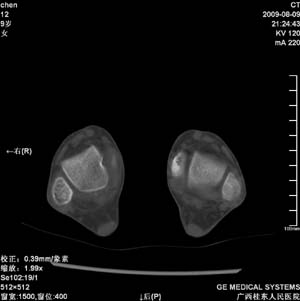

标题: PED2867:右侧内踝肿胀,骨质改变,请各位老师会诊 [打印本页]

标题: PED2867:右侧内踝肿胀,骨质改变,请各位老师会诊

九岁小朋友,近期左侧内踝疼痛,局部肿胀,平时无特殊,近期经常溜干冰

对不起,是右侧内踝肿胀

双踝关节骨质及发育未见异常。

左侧内踝密度增高,请结合临床!